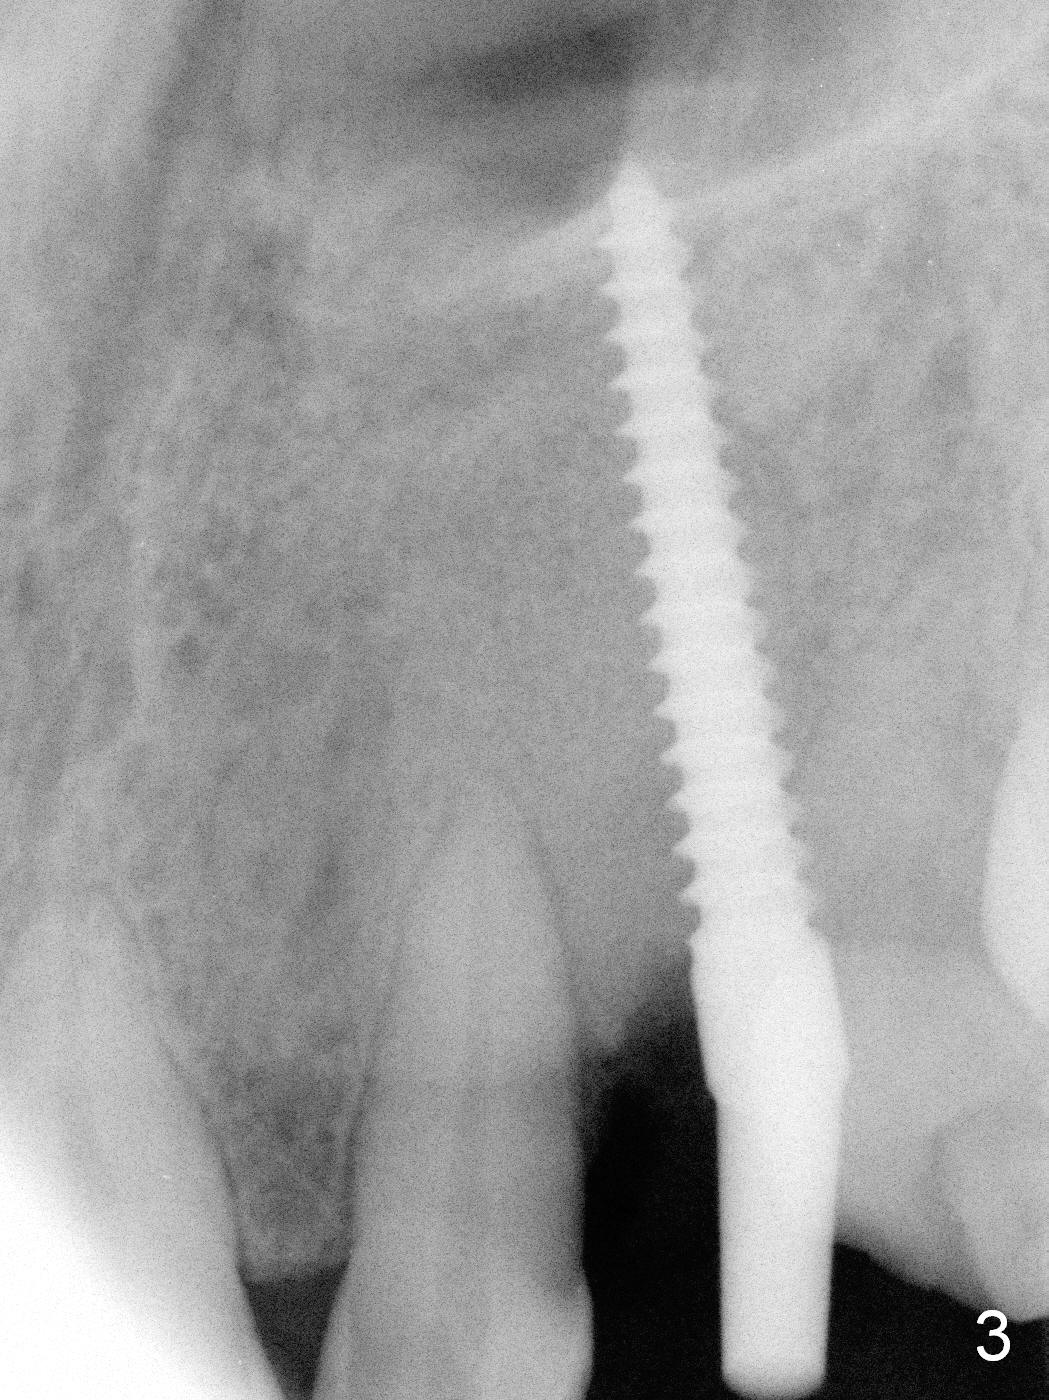

Intraop PA shows that the nasal floor is perforated (Fig.3). The patient experiences bilateral nasal obstruction. Sneezing produces trace of hemorrhage from the left nostril and large amount of secretion from both nostrils. The nasal speculum is misplaced in the clinic. Clinical nasal floor perforation cannot be confirmed. After abutment preparation, an immediate provisional is fabricated. Afrin is prescribed. Post-op instruction includes continuing Amoxicillin and Chlorhexidine rinse. A few hours postop, the patient reports no abnormality.